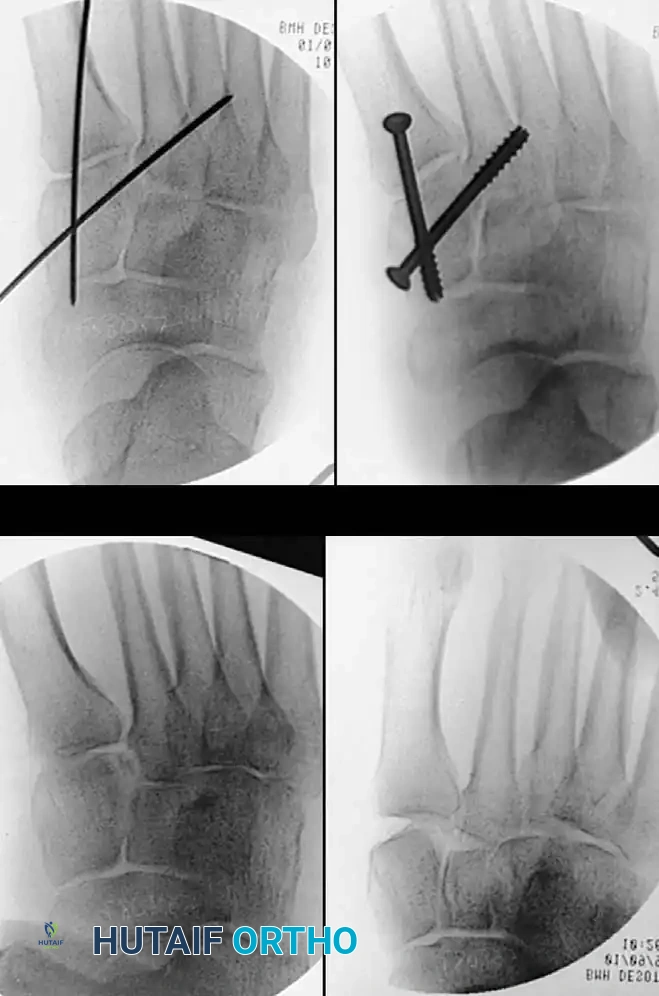

Fig. 86-36 Open reduction and internal fi xation of type III navicular fracture. A and B, Preoperative radiographs. C, Semicoronal CT scan showing comminution of body of navicular. D and E, Postoperative radiographs.

Fig. 86-36: Open reduction and internal fixation of a Type III navicular fracture. Note the severe comminution on the preoperative CT and the restoration of the medial column length postoperatively.

If severe comminution leads to collapse of the navicular and subsequent medial column shortening, structural bone grafting (autograft from the iliac crest) is mandatory. Temporary spanning fixation to the talus or cuneiforms, or the application of a small medial external fixator, may be required to maintain column length during healing. Prolonged recovery and persistent midfoot stiffness are common sequelae.